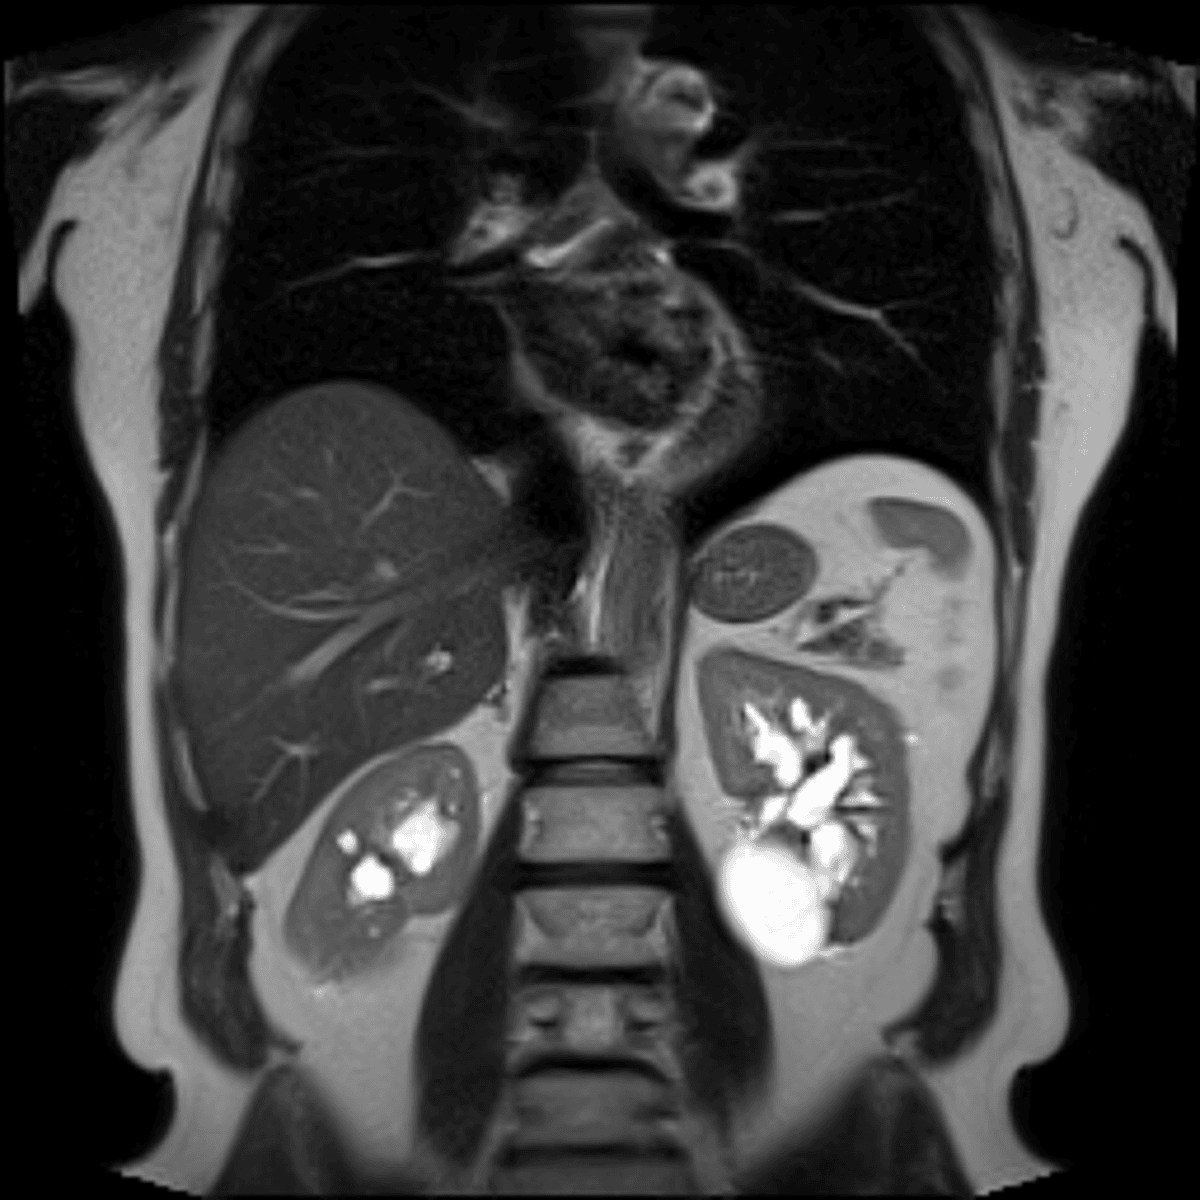

Cysts are fluid-filled sacs or pockets that can form in various parts of the body. Most cysts present little or no discomfort and are harmless. The majority disappear without treatment within a few months. Sometimes these cysts can rupture and release blood, known as hemorrhagic cysts. A hemorrhagic kidney cyst can be due to recent trauma.

Women have two ovaries - each about the size and shape of an almond - on each side of the uterus. Ovarian cysts are fluid-filled sacs or pockets inside an ovary or on its surface. Many women have ovarian cysts at some time in their lifetime. Most ovarian cysts present little or no discomfort and are harmless.